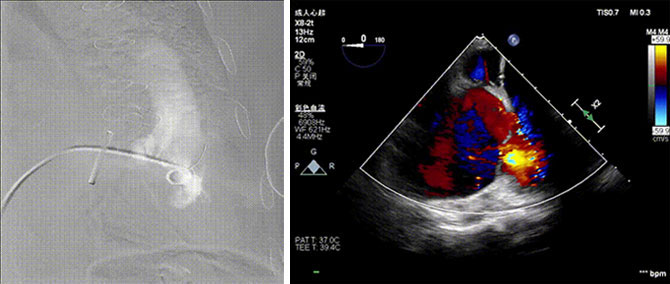

手术全程在经食道心脏彩超(TEE)和数字减影血管造影(DSA)的指引下进行。全麻后,郭惠明、刘健团队在患者右侧颈静脉穿刺,采用静脉入路将输送器送入右心,在进入右室后释放室间隔锚定装置,旋转输送器,使得锚定装置对准室间隔面。而后释放前瓣夹持件,确定夹持件位于右室侧,释放人工瓣膜盘片,再使用DSA和超声确认盘片位置,同时调整瓣膜的同轴性。紧接着在DSA和超声的监视下调整室间隔锚定件贴合室间隔,释放室间隔锚定装置。再次确认瓣膜的稳定性和同轴性后,释放瓣膜并将输送器撤出体内,最终完成LuX-Valve Plus三尖瓣人工瓣膜植入(图2-5)。手术获得圆满成功。患者在手术室即刻拔除气管插管,术后超声提示:人工三尖瓣瓣膜同轴性良好,瓣架固定牢靠,无反流和瓣周漏。

图2 术前DSA 图3 术前超声